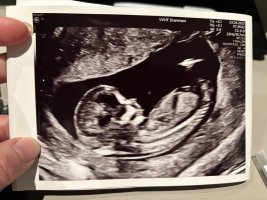

Gutt! Men det skal stadfestes på neste ul om 2 uker. Det kunne være navlestrengen de så, men de sjekket med temperatur (?) /farger og det så ut til at navlestrengen lå lenger opp.Og hva får du?![]()

Blir spennende å høre hva de sier om 2 uker da!Gutt! Men det skal stadfestes på neste ul om 2 uker. Det kunne være navlestrengen de så, men de sjekket med temperatur (?) /farger og det så ut til at navlestrengen lå lenger opp.

La inn begge bildene mine og fikk jente på begge. Blir veldig spennende altså.Og hva får du?Nå har vi fått vite kjønn, og det var det motsatte av det nub teorien viste meg. Haha!

Det gjorde jeg også, og fikk samme svar som jeg mente ut fra nub teorien. Altså det motsatte av det som ble stadfestet på ultralyd i dag. Haha.Man kan spørre chat gpt om å gjøre analyse av ultralydbildet faktisk.La inn begge bildene mine og fikk jente på begge. Blir veldig spennende altså.